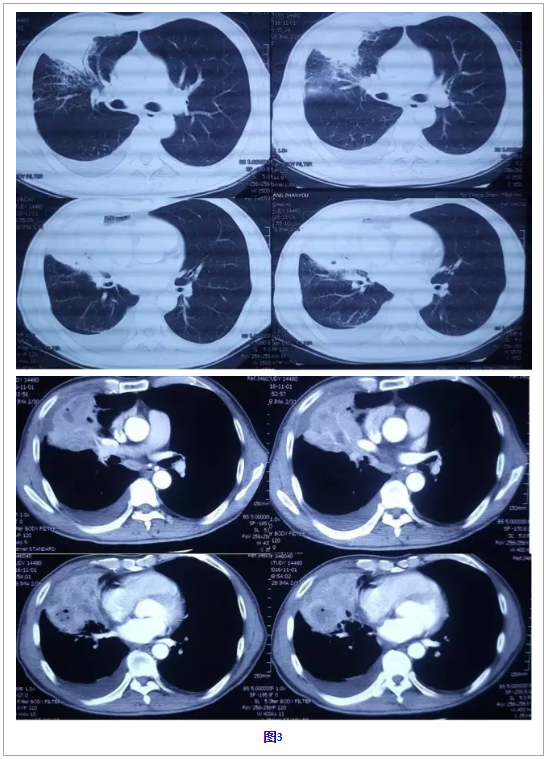

转至当地某三甲医院就诊(10 月 19 日-11 月 20 日),痰培养「卡他布兰汉氏菌(头孢曲松、头孢唑林、哌拉西林敏感)」,支气管镜(10 月 25 日)提示右肺中叶开口粘膜充血、水肿,表面粗糙,有污秽色小结节,管腔狭窄,病原学阴性。11 月 1 日复查胸部 CT(图 3)右肺中叶支气管闭塞,未见异常强化肿块影,右肺中叶及邻近肺组织实变伴内坏死,较 9 月 7 日范围变大,右肺中叶强化结节影,强化程度与同层面血管相类似,考虑病变累及血管所致,右肺胸腔积液并右肺下叶部分膨胀不全。